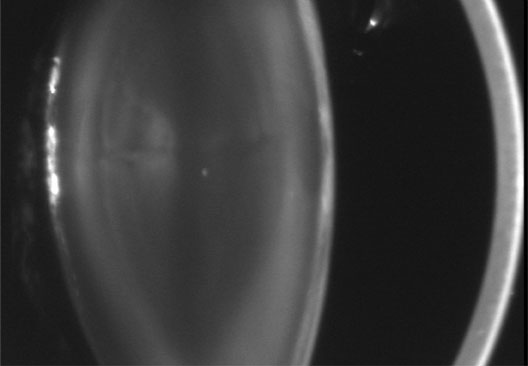

Anterior lenticonus (Figs. 8 and 9) is considered an integral part of AS. The anterior capsule thins and allows the lens to bulge into the anterior chamber, using the pupil as a mold.53 Electron microscopy of the renal glomeruli and anterior lens capsule can confirm capsular thinning and dehiscences.54,55 Anterior lenticonus is typically diagnosed in the second and third decades of life, when it causes clinically significant decreased vision,56 but it may be present in adolescence and result in spontaneous rupture of the anterior lens capsule.57 Posterior subcapsular cataract occurs quite frequently; however, many patients receive glucocorticosteroids for their renal condition, which may play an etiologic role in these cataracts. Additional ocular features described in XLAS include other corneal dystrophies, microcornea, corneal arcus, iris atrophy, posterior lenticonus, spontaneous lens rupture, spherophakia, a poor macular reflex, fluorescein angiogram hyperfluorescence, electrooculogram and ERG abnormalities, and retinal pigmentation abnormalities.58

Fig. 8. AS. The thinned lens capsule and anterior cortex protrude centrally into the anterior chamber and an additional small, central, posterior, subcapsular opacity in a 38-year-old male with AS (Scheimpflug image).

Fig. 9. AS. Oil-droplet appearance of anterior lenticonus in retroillumination. (Courtesy of Dr. N. Meadow, Manhattan Eye and Ear Hospital, New York, New York.)